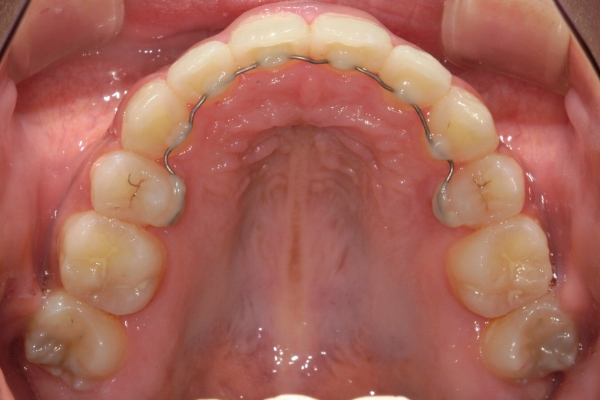

歯の移動を終えると、矯正装置をすべて取り外します。装置の撤去後は、後戻りを防止して歯並びを安定させるために、保定装置(リテーナー)を使っていただきます。 保定開始後すぐは1~3か月毎、歯列の後戻りが少なくなってからは3~6か月毎にご来院いただき、噛み合わせと保定装置の状態をチェックします。 保定期間の長さは治療内容にもよって変わりますが、一般的には矯正治療に要した期間と同じ程度必要になることが多いです。

BEFORE

治療前

PROCESS

半年

AFTER

治療後

上顎前歯が1cm近く前方に出ており、叢生を改善しつつ前歯を大きく引っ込めるために上下顎小臼歯の抜歯が必要と診断しました。治療後は、主訴であった前歯の突出と奥歯の噛み合わせのずれが改善され、上下の咬合関係が安定しました。